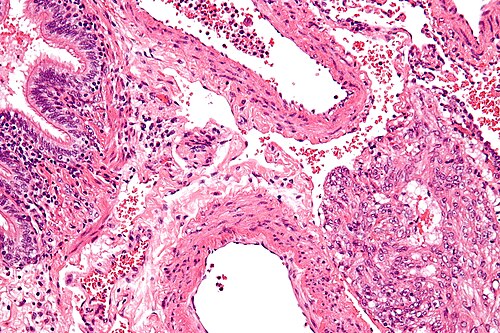

High magnification

High magnification. H&E stain.